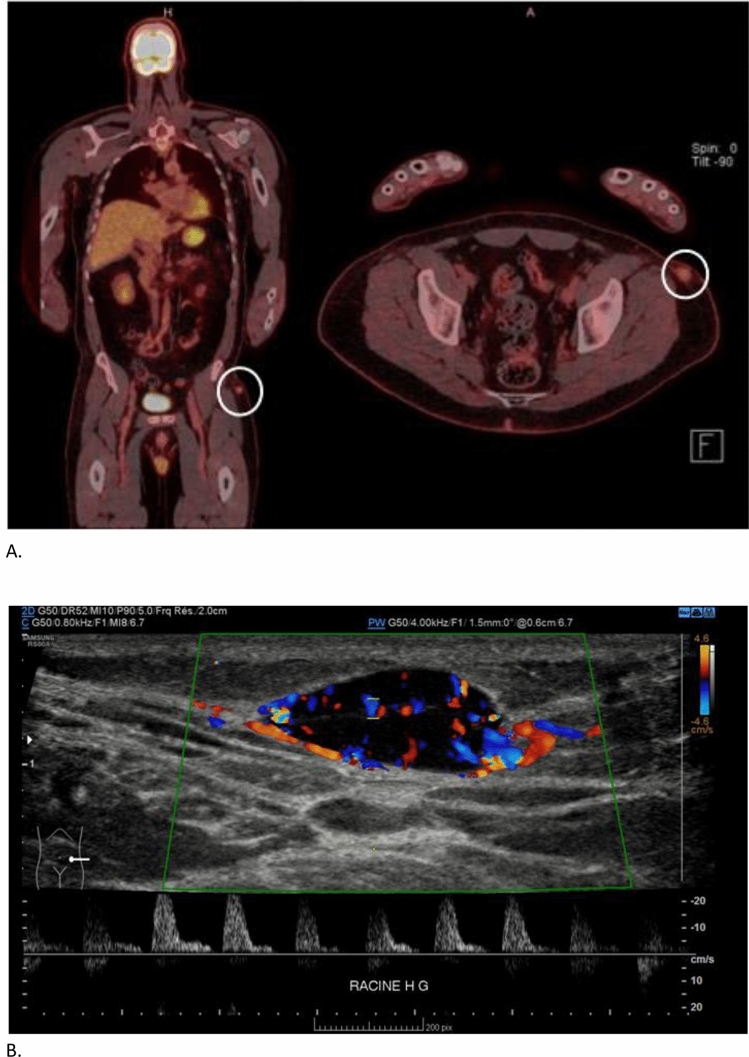

肿瘤诱导骨软化症(TIO)是一种罕见的获得性副肿瘤综合征,由间质肿瘤分泌一种名为FGF23的磷化激素引起。患者表现为骨痛、脆性骨折和肌肉无力。生化结果显示低磷血症,血清碱性磷酸酶升高,骨化三醇降低。我们报告一例44岁的男性,因急性腰痛到急诊室,显示D2和L5之间广泛的软骨下骨折。调查显示部分范可尼综合征;然而,他有严重的低磷血症,低1,25- oh维生素D和升高的FGF23水平提示诊断为肿瘤诱导的骨软化症。在范可尼综合征的背景下,最初通过PET-CT检查发现左腿皮下病变,以排除恶性肿瘤。肿瘤切除术使电解质紊乱在手术后几天内得到完全解决。本病例显示TIO可能表现为部分范可尼综合征,强调了在低磷血症病例中检测其他电解质的重要性,以及在部分范可尼伴严重低磷血症病例中寻找TIO的必要性。

Tumor-induced osteomalacia (TIO) is a rare acquired paraneoplastic syndrome caused by a mesenchymal tumor secreting a phosphaturic hormone called FGF23. Patients present with bone pain, fragility fractures and muscle weakness. Biochemical results show hypophosphatemia, raised serum alkaline phosphatase and reduced calcitriol. We report the case of a 44-year-old man who presented to the Emergency Departement with acute low back pain revealing extensive subchondral fractures between D2 and L5. Investigations showed partial Fanconi syndrome; nevertheless, he had profound hypophosphatemia, low 1,25-OH vitamin D and raised FGF23 levels suggesting a diagnosis of tumor-induced osteomalacia. A subcutaneous lesion was identified in the left leg on a PET-CT initially performed to rule out malignancy in the context of Fanconi syndrome. Tumorectomy enabled complete resolution of the electrolyte disturbances within days of surgery. This case shows that TIO may present as partial Fanconi syndrome, highlighting the importance of testing other electrolytes in cases of hypophosphatemia and the need to look for TIO in cases of partial Fanconi with severe hypophosphatemia.